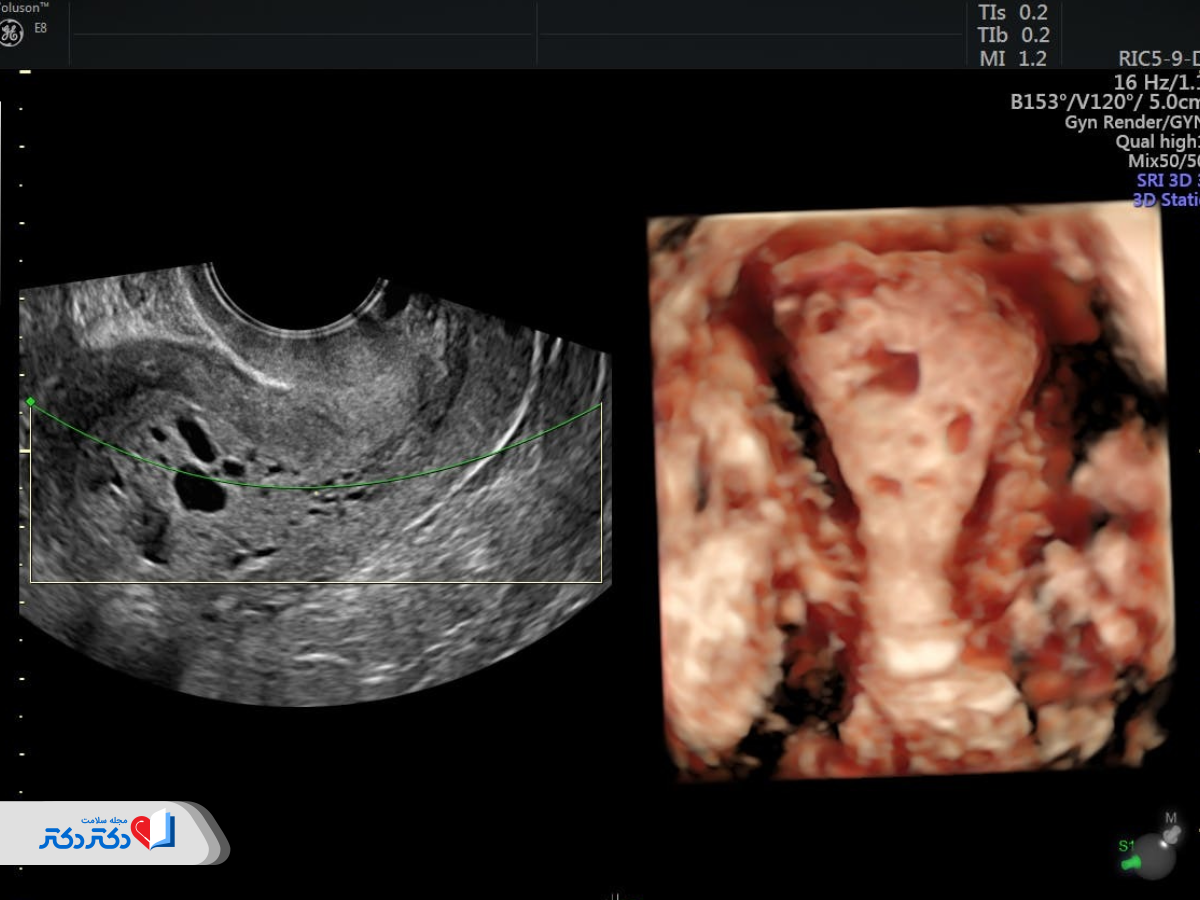

سونوگرافی ترانس واژینال

سونوگرافی ترانس واژینال با ورود پروب سونوگرافی به داخل واژن انجام میشود؛ بنابراین تصاویر بهدست آمده دقیقتر خواهند بود.

اگر پزشک متخصص زنان حین سونوگرافی ترانس واژینال بینظمیهایی را مشاهده کند، برای تشخیص دقیقتر سرطان رحم بیوپسی آندومتر را تجویز خواهد کرد.